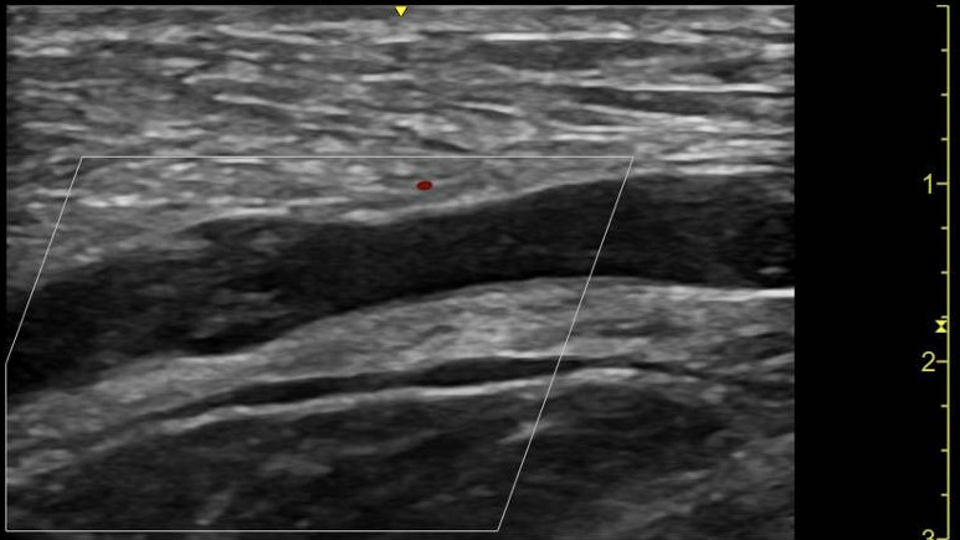

With a provisional diagnosis of sepsis, resuscitation with crystalloid intravenous fluids (NaCl) was initiated. Point-of-Care Ultrasound (PoCUS) demonstrated cobblestoning and subcutaneous air with dirty shadowing of the entire upper limb and right-side chest wall3 (Figure 3), suspicious for Necrotizing Fasciitis, as well as a non-compressible proximal part of the axillary vein suspicious for concurrent thrombus (Figure 4), likely secondary to swelling and immobility. Extended PoCUS showed a  hyperdynamic heart without effusion, LV dysfunction, or significant right heart strain.

Point-of-Care Ultrasound (PoCUS) has emerged as a valuable tool in the rapid diagnosis of Necrotizing Fasciitis, especially in the emergency department setting. PoCUS allows for bedside imaging, which can significantly reduce the time to diagnosis and subsequent treatment. In this case, PoCUS was instrumental in identifying the hallmark features of Necrotizing Fasciitis, including cobblestoning, subcutaneous air with dirty shadowing, and non-compressible veins suggesting thrombus formation7. These findings prompted immediate surgical consultation and expedited surgical intervention. The utility of PoCUS extends beyond diagnosis to include ongoing management and monitoring of disease progression. It provides real-time information about the extent of infection and can be used to guide fluid resuscitation, identify complications, such as abscess formation, and monitor the effectiveness of therapeutic interventions. Additionally, PoCUS can be used to evaluate cardiac function and detect hemodynamic instability, as was done in this case6.